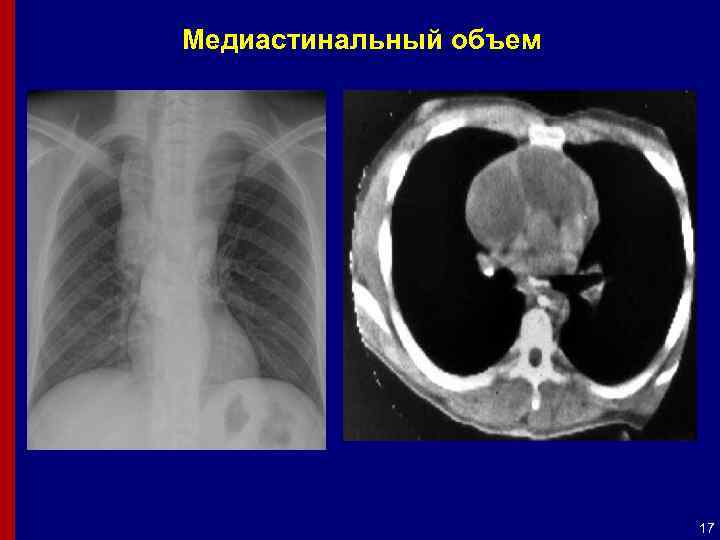

Медиастинальный объем 17